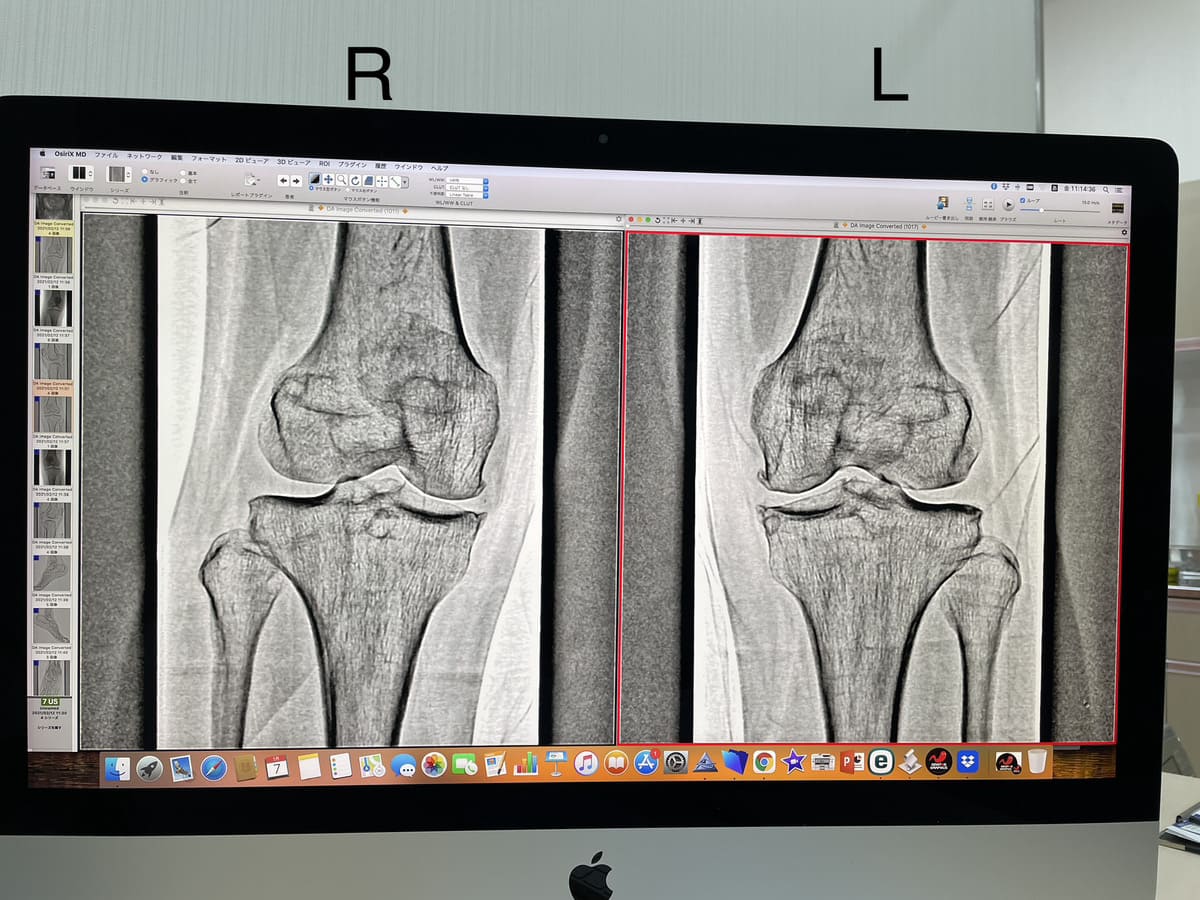

はい、元々は左膝の方が悪くて。今回のレントゲン診断でも骨の状態は左の方が悪い、と言われました。

とりあえず今は右の方が圧倒的に酷い症状として出てきていますが、決して左が良い訳ではありません😢

ご参考までにレントゲン写真も載せます。

(3年前のものですが、今回と見比べても大差ないと言われました)

全身のバランスをイメージすると

かなり右寛骨を前に反り出すようなパワーを臀部にお持ちのようですね。

レントゲンをみても左脛骨の細さに「左右で柱の太さが違う」という表現が露骨になっていて驚かされました。そして左股関節で受け止めたい荷重をおそらく左小臀筋群で受け止めているのかなと。(ダンスの負荷を思うともの凄い身体能力を感じますっ)左股関節は外旋してるので内旋方向に正位置がありそうです。